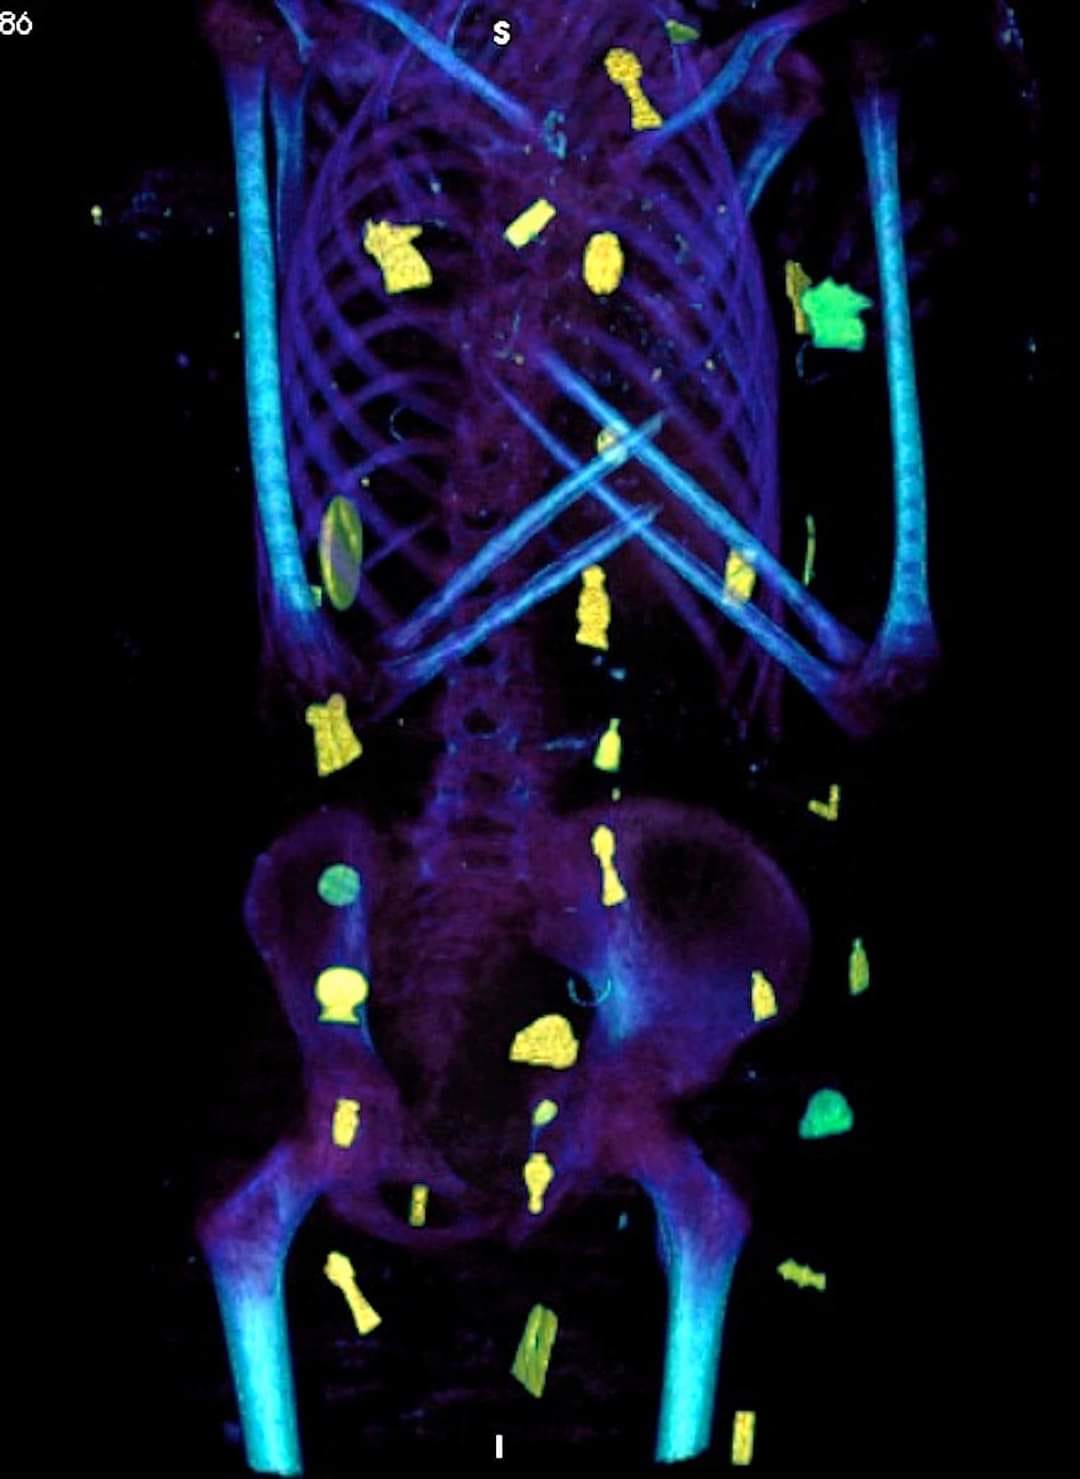

ونشرت إدارة المتحف المصري بالتحرير، عبر صفحتها الرسمية على الفيس بوك، صور اآأشعة المقطعية لمومياء الصبي الذهبي كالتالي: -

وأشارت إدارة المتحف المصري بالتحرير، إلى أن آشعة المومياء لصبي بينت أن الطفل توفي عن عمر يناهز 15 عاما، وأنه تم تحنيطه بإتقان كبير وقد حرص المحنطون على الإبقاء على القلب الذي تمت رؤيته في صور الآشعة بداخل تجويف الصدر.

تمتعت هذه المومياء بطقوس جنائزية مميزة تمكنها من البعث والحياة الأخرى حسب معتقدات المصريين القدماء، بالإضافة إلى إظهار المكانة الاجتماعية الرفيعة لصاحب المومياء فهو صبي حظي بطقوس جنائزية عالية المقام، إلى جانب حالته الصحية الجيدة، حيث كان يتمتع بأسنان وعظام سليمة وبلا علامات تدل على أمراض أو أعراض سوء تغذية.